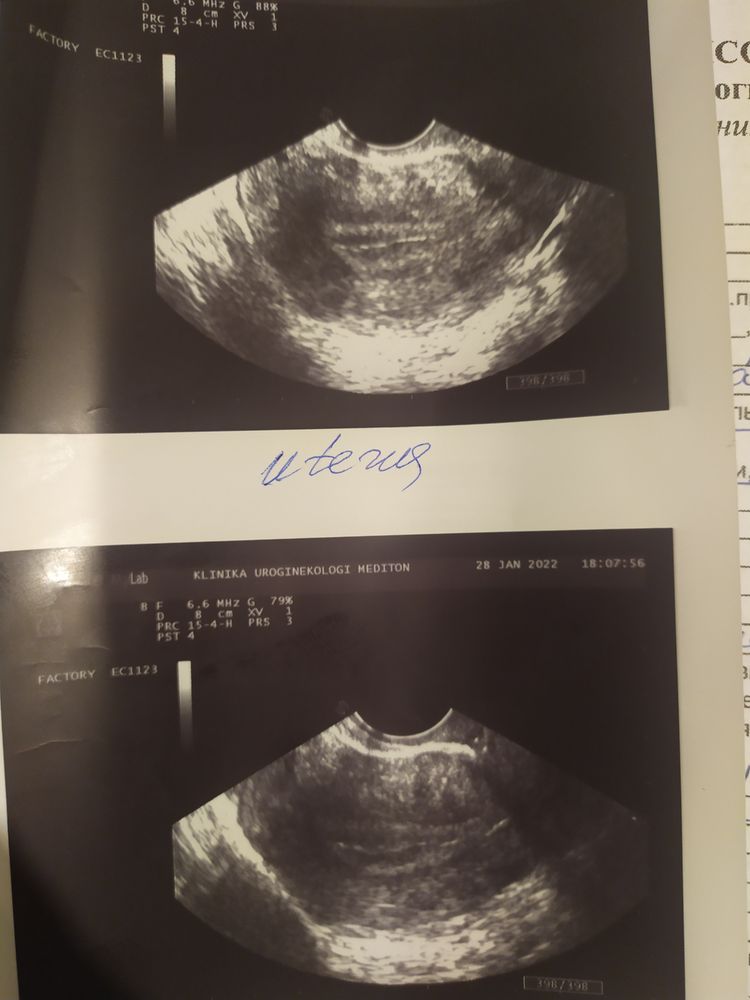

Поехала к Г,она посмотрела и сказала,что у меня молочница,а по УЗИ ничего нет и быть не может,показатели не беременные....Тем более ЖТ слева,где у меня нет трубы.А тесты мол полосатые из-за сбоя.

Эндометрий 15 - это говорит за беременность. Полоски тоже за беременность. Тесты могут быть разными. По ним динамику смотреть бесполезно. Вообще , протокол узи плохо видно. 20 антральных фолликулов? Серьезно? Эндометрий 15 и 20 антральных фолликулов? Это все вообще не вяжется между собой. Сдавайте динамику хгч. Если все хорошо, дней через 10 снова на узи к другому специалисту.

Последнее УЗИ делала год назад,на 7 ДЦ было 10-15 фолликулов.Я вот сравнивала с ранними своими УЗИ,у меня матка сейчас увеличена.

Диана Артюх, антральные фолликулы - показатель первой фазы цикла. Но при этом эндометрий 3-6 мм, если еще доминантного фолликула нет. А беременность - это прогрессирующая вторая фаза. В нет антральных фолликулом, жт от 18 мм, эндометрий от 10 мм. 15 - это прямо беременный эндометрий.